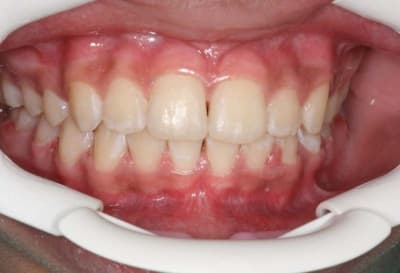

3°) phase

contention

@+ Bjc

c'est le mm. patiente

la coloration des dents est assez remarquable

P.S.: j'avais à l'époque un Fuji mono-objectif

les photos de la contention ont été prises avec un Canon 1000 objectif Macro

les couleurs ne sont pas tout à fait les mm.

mais les dents ont gardé la mm. forme et les taches sont reconnaissables

@+ Bjc.